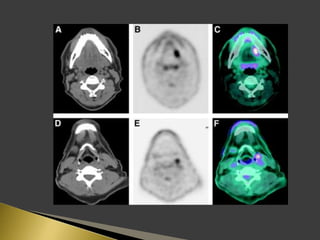

 PET using the radio-labeled glucose analog 18F-FDG has great

importance in lymph node imaging.

 PET supplies a semi-quantitative metabolic characterization of

tissues that may help to predict tumor behavior.

 The sensitivity and specificity of 18F-FDG PET for identification

of lymph node metastases on a neck level-by-level basis were

higher than those of CT/MRI.

 The incorporation of functional information derived from PET

has the potential factor to improve prognostic stratification and

treatment planning for patients.

 Patients were instructed to fast for 6 h before the PET study.

 18F-FDG was administered intravenously.

 For PET/CT scans, oral contrast was administered to patients

during the uptake time.

 No IV contrast material was administered for CT scans.

 Head to mid thigh scans were obtained for all patients.

 PET and CT images were acquired 50 min after the injection of

18F-FDG.

 PET, CT, and fused PET/CT images were available for review

and were displayed in axial, coronal, and sagittal planes.

 PET data were displayed as non-corrected and attenuation-

corrected images as well as in a rotating MIP.

 Area of increased 18F-FDG uptake with intensity higher than

that of surrounding tissues and did not correspond to the

physiologic bio-distribution of the radiotracer, were defined as

positive.

 18F-FDG activity only in areas of the physiologic tracer bio-

distribution or no sites of increased uptake were considered

negative.

 The highest activity within a region of interest was measured.

 The standardized uptake value (SUV) was determined as the

highest activity concentration per injected dose per body weight

(kg).

 18F-FDG uptake was graded visually on the following 5-point

scale:

 0-definitely benign, no uptake.

 1-probably benign, 2.3 (range, 1.4–4.0).

 2-equivocal, 2.6 (range, 1.4–4.4).

 3-probablymalignant, 3.5 (range, 2.1–7.9).

 4-definitely malignant, 6.6 (range, 2.6–24.5).

 SUV of 3.1 was used as the cutoff for positive PET results.